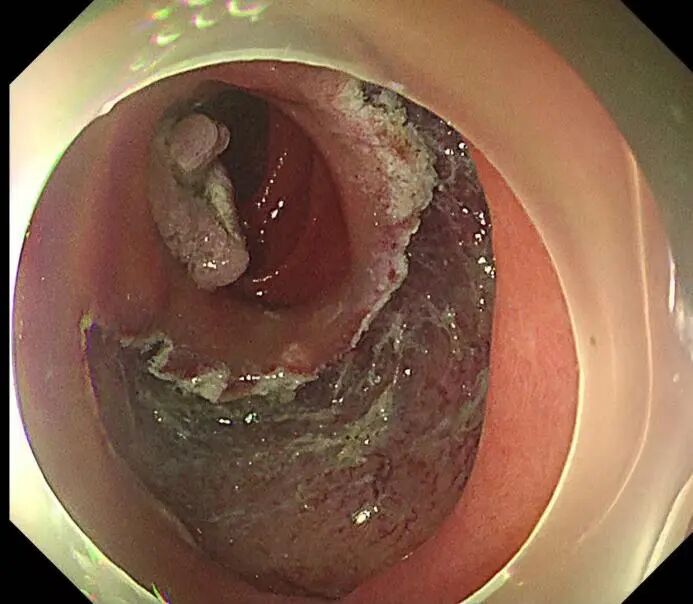

手术开始,尽管十二指肠降部空间有限,病变较大,且十二指肠部位血供丰富,但在SPEED技术的辅助下,徐美东教授用稳定的控镜和精妙的微操,如“庖丁解牛”般逐步推进,边注射边剥离,全程视野清晰可见,最终仅耗时半小时将该病变整体剥离并完整取出,完成这场“刀尖上的舞蹈”。创面干净、几乎无出血,没有丝毫肌层损伤,堪称内镜手术的“完美范本”。

2-SPEED技术边注射边剥离

3-病变环周切开后